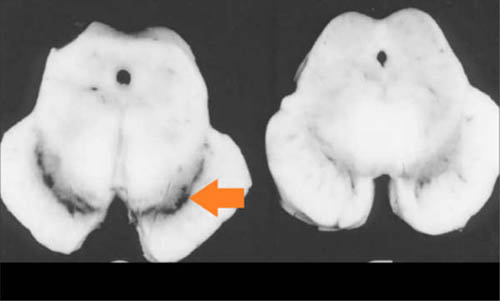

正常人及病人中脑的解剖图对比。箭头所指部位是正常人的黑质,相比之下,病人的黑质消磨丧失(来源:Memorang)